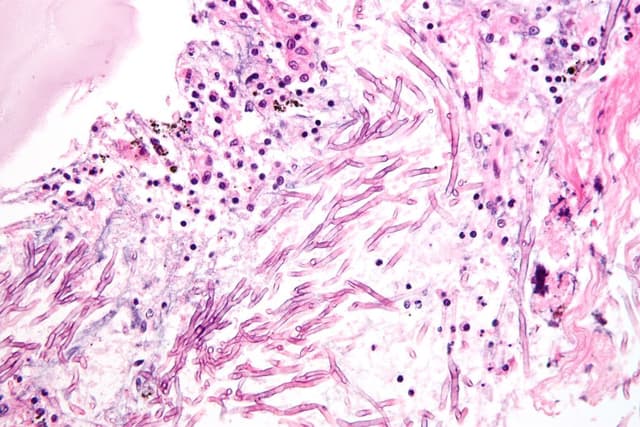

داء الرشاشيات: الأسباب والأعراض والتشخيص والعلاج